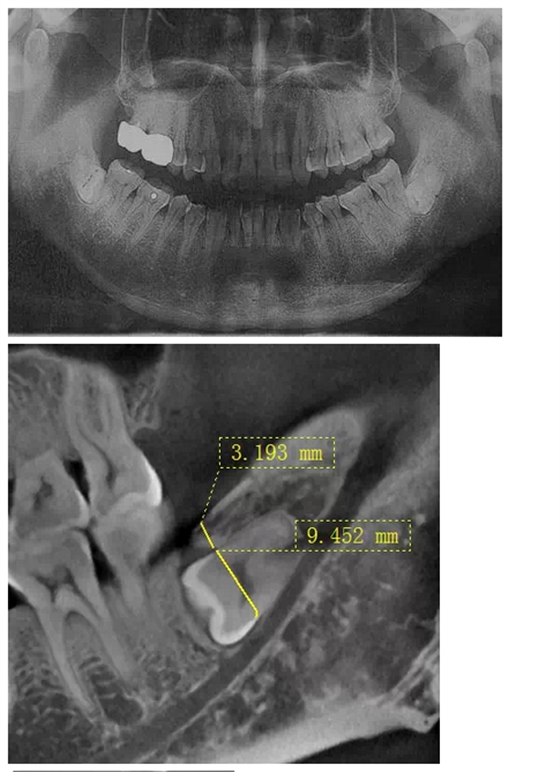

曾有這樣一位痛苦的中年患者,因雙側(cè)胸悶不適困擾二十余年,多處求醫(yī)無果,一次偶然體檢的機(jī)會(huì),拍得口腔曲面體層片(全景片,圖一),顯示下頜雙側(cè)各有一顆水平埋伏阻生智齒,醫(yī)生建議擇期拔除。但患者更關(guān)心此二顆智齒是否是引起自己不適癥狀的原因,均被告知不敢肯定,無法從西醫(yī)角度解釋有何關(guān)聯(lián)。但痛苦驅(qū)使著患者自己去查閱了大量中醫(yī)資料,查得此下頜角處為一穴位,患者遂認(rèn)為可能是這二顆牙齒點(diǎn)中了此穴,導(dǎo)致自己胸悶不適,說服自己之后,來我院就診要求拔除。

沒有CT,在全景片上評(píng)估右下智齒與下牙槽神經(jīng)管距離很近,告知各樣風(fēng)險(xiǎn),患者表示理解并簽字。常規(guī)手術(shù)切口,翻瓣,露得一部分牙冠,去骨后,多次小心翼翼檢查車針深度,使冠根分離,去除牙冠,進(jìn)入取根階段,多次輕力試挺,均無動(dòng)靜,只知牙根與下牙槽神經(jīng)管很近,卻不知具體的三維關(guān)系,所以只好小心翼翼地找間隙,此舉進(jìn)展龜速,如履薄冰,筋疲力盡,猶如兩驅(qū)小轎車行駛在泥濘的小道上,想給力卻打滑。后來還是團(tuán)隊(duì)的力量,輪番上陣,最終全部拔除,拔除后才得知原來是兩個(gè)牙根向內(nèi)直角彎曲,牢牢卡住了中間的牙槽中膈?;颊叩诙祀m然術(shù)后反應(yīng)較大,但是非常開心地告訴我們右側(cè)胸悶有明顯好轉(zhuǎn),而且右側(cè)嘴唇?jīng)]有麻木,所以要求傷口恢復(fù)好之后馬上將左側(cè)的智齒拔除。這給我們帶來了安慰的同時(shí),也給了我們更大的挑戰(zhàn)。

在拔牙一月后,鳥槍換大炮,診所引進(jìn)了三維CT,左側(cè)智齒在拍了CT后,前后頰舌上下關(guān)系就一目了然,此牙更難拔除,因?yàn)橥耆穹▓D二),其上面覆蓋有3mm厚的牙槽骨,其下緣與下牙槽神經(jīng)管緊緊相連,較危險(xiǎn);牙冠前緣與第二磨牙遠(yuǎn)中根也緊緊相連,后緣牙根向上翹;整個(gè)牙齒偏頰側(cè),頰側(cè)皮質(zhì)骨板較厚(圖三),舌側(cè)骨板也較厚,測好牙冠頸部上下距離約為9.5mm。